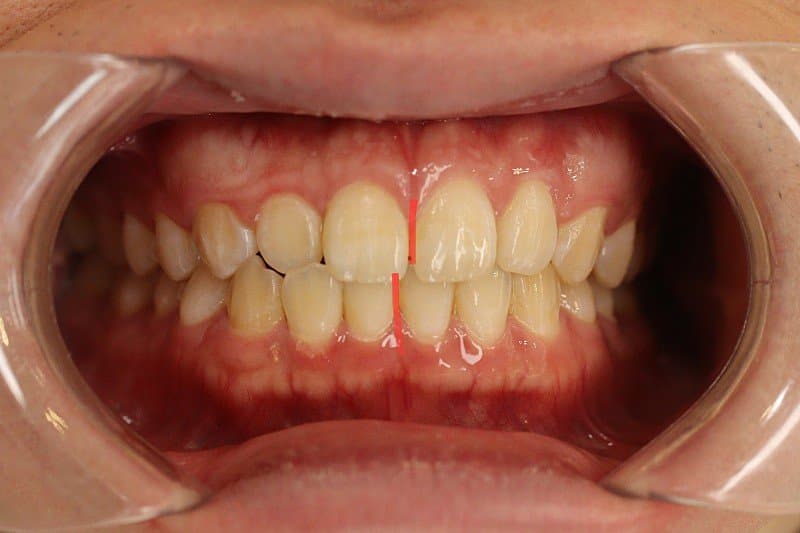

)치아 뼈가 전방으로 많이 나온 상태인가요?

)골격적으로 나온건가요?

)교정으로는 개선은 힘든가요? 해결하려면 양악이나 ASO수술이 필요한가요?

1. 전방으로 많이 나왔다고 볼 수도 있지만 심미적으로 봤을 때 치료를 하지 않아도 되는 정도입니다. 본인이 현재 안모에 불만족스럽다면 이는 치료의 대상입니다.

2. 해당 정도로는 교정으로 개선이 불가능하며 양악을 하셔야 합니다.